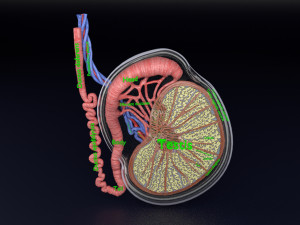

Breast anatomy histology detailed labelled precise to scale model 3D Модель

This is a 1:1 scaled model of right breast cut opened in sagittal plane to reveal its internal antomy and histology (schematic). The deeper parts and fascial layers are also depicted to give a very detailed approach to the model. The full layers starting from skin, nipple areola, till intercodtal muscles and ribs are also depicted.

breast mammary gland female chest wall anatomy human medical science reproductive genitalia muscle fascia milk nipple areola subcutaneous fatДо даного товару немає коментарів.